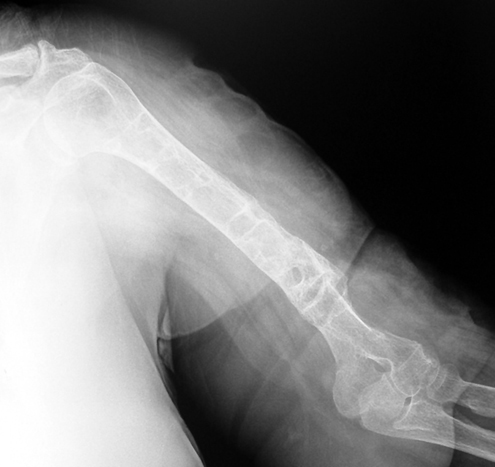

Pseudarthrosis of fracture and pseudarthrosis treatment is currently important problem for orthopedic surgery. Various treatment modalities have been described for pseudarthrosis treatment. All of the treatment methods include high complication rates and additional problems. Leg-length discrepancy, deformity and soft-tissue loss and chronic infection can concomitance with pseudarthrosis. Many internal or external fixation techniques have been described for pseudarthrosis. Debridement and resection of bone fragment from the pseudarhtosis area vascularized or nonvascularized fibula graft, vascularized muscle flaps, bone grafting followed internal fixation techniques make a option for treatment of pseudarthrosis treatment. But these treatment modalities may not correct deformity and leg-length discrepancy. Recently, ilizarov techniques which is basis depend on distraction osteogenesis , bone segment transport or acute shortening after the resection at the site of pseudarthrosis combined with lengthening at another level of bone have been used. These treatment techniques may include some advantage for problems of infection, leg-length discrepancy, soft-tissue loss, and joint contracture.